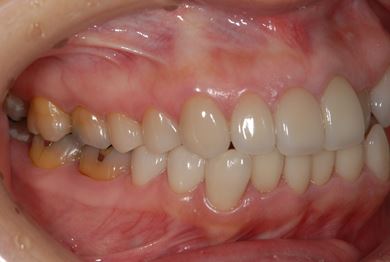

セラミックの症例写真 SHINBI

セラミック治療+ラミネートベニア治療

| 治療内容 | ジルコニアオールセラミッククラウン1本(オールセラミック用土台1本)、オールセラミッククラウン9本(オールセラミック用土台1本)、オールセラミックラミネートベニア11本 | ||||||||||||||||||||||||||||||||